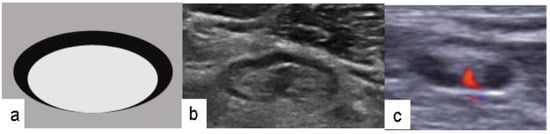

- Ecanow, J.; Abe, H.; Newstead, G.M.; Ecanow, D.B.; Jeske, J.M. Axillary Staging of Breast Cancer: What the Radiologist Should Know. Radiographics 2013, 33, 1589–1612. [Google Scholar] [CrossRef]